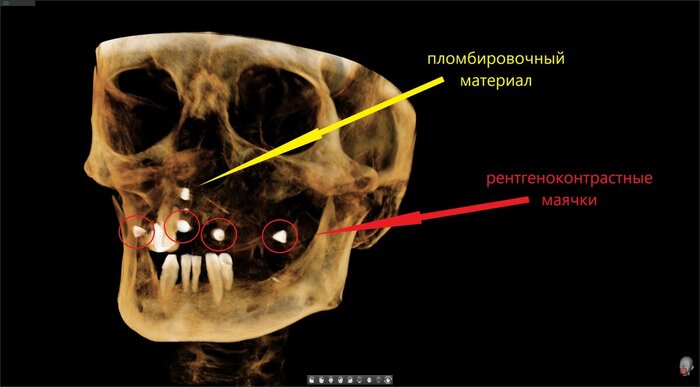

Получилось так, что сверху всего 8 зубов, по 4 с каждой стороны. Чёрная точка (которую вы точно увидите, скос эмали на зубе 1.1) - конструктивные особенности, всё это будет закрыто пломбировочным материалом. Зуб 1.1 - дополнительный имлантат, который потом планируем убрать. Он нужен лишь для усиления, ибо торк полноценный был получен только на одном из остальных 6-ти установленных.

Напоминаю - протезы временные адаптационные

Так же важный момент - верхний протез соприкасается с нижним только в точках полученного торка (их всего 2), остальное "на весу" и жевать не способно.

Шахты имплантатов закрыты временным материалом на 2 дня, он не очень эстетичный по цвету.

В понедельник винты будут подтянуты, а шахты закроются постоянным пломбировочным.

Поднутрения, дефекты слизистой - на то протезы и временные адаптационные, что костная ткань должна перестроиться и прийти в себя перед постоянным протезированием.